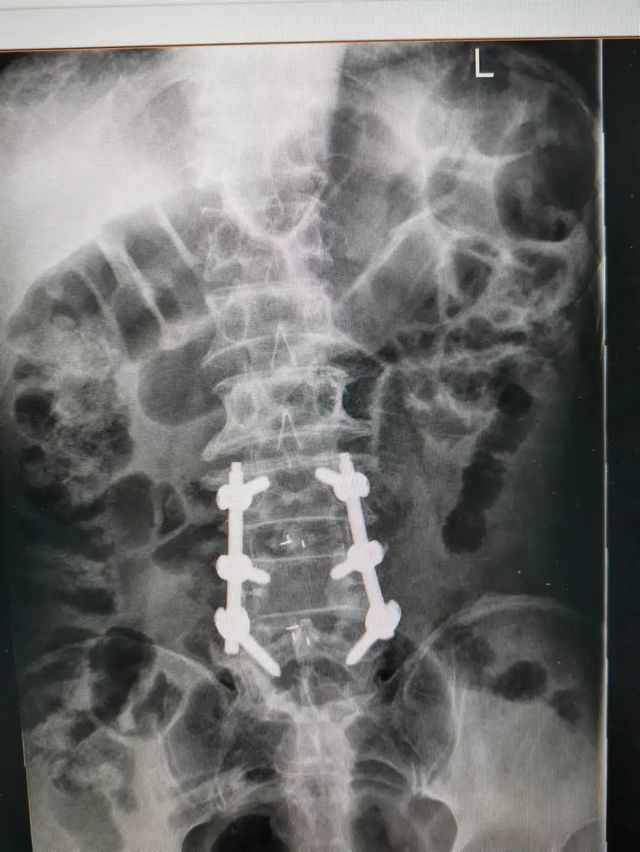

杨先生术后拍片

由于杨先生的病情严重,需住院治疗。杨先生入院后,泸州市中医医院骨伤二科科主任杨陈一制定了手术计划,决定脊髓型颈椎病的手术从前路切开减压,颈3/4 、颈4/5、 颈5/6、 颈6/7椎间盘切除,椎间融合,钢板内固定术手术,而腰椎管狭窄症经后路切开减压,腰3/4、腰4/5椎同盘动除,椎间融合、钉棒系统内固定术。